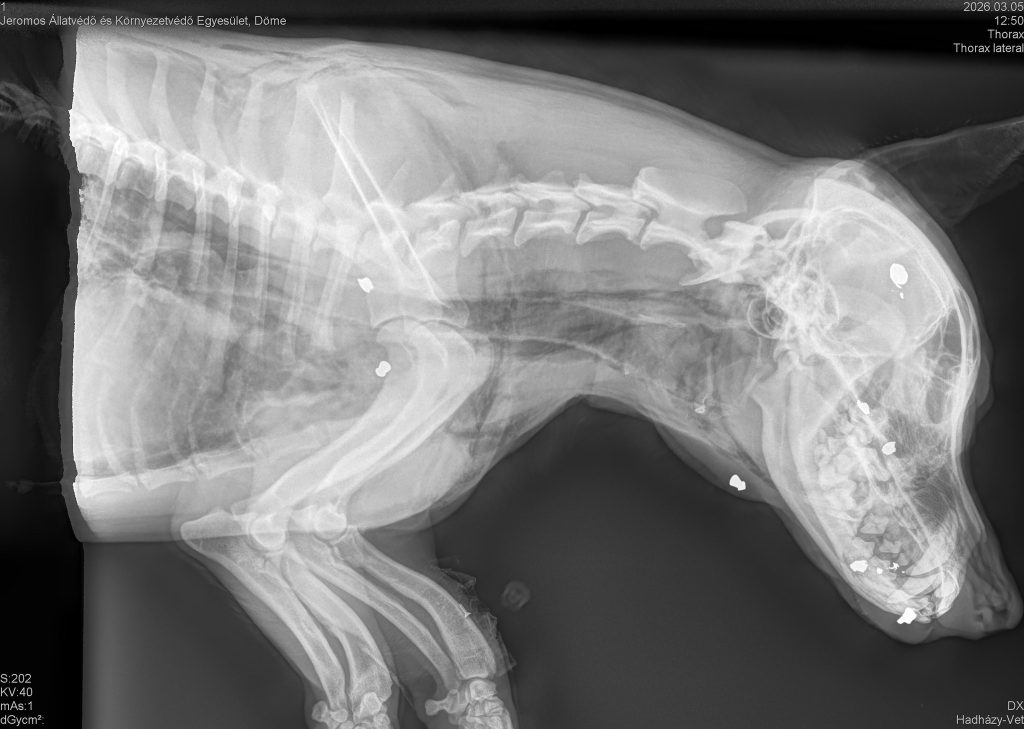

A mai napon délelőtt egyesületünk bejelentést kapott Bácsbokodról, hogy egy sérült kutyát találtak az út mellett. Pontosabban a Fő úton a Csintalan tanya felől Bácsbokod központja felé a sertéstelepnél sikerült megfogni. A szeme be van vérezve, furcsán veszi a levegőt, egy zöld hulladékos nejlonzacskó van a nyakára kötve. Azonnal indultunk érte, utunk rögtön Szekszárdra a Központi Állatklinikára vezetett, ahol a kutyát megvizsgálták. A röntgenfelvételek során kiderült, hogy a kutyában minimum 6 lövedék látható, egyik átszakította a légcsövet, ezért a bőre alatt kiáramlik a levegő.